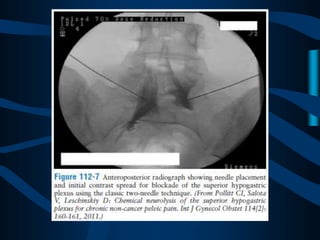

ABORDAJE CLASICO

DE DOS AGUJAS